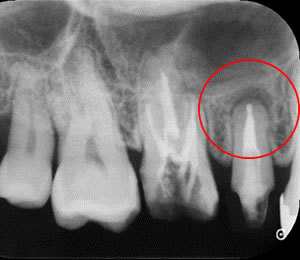

根管充填後

MTAセメントにて根管充填しました。根尖まできちんと充填されているのがわかります。この後セラミッククラウンを装着する予定です。病巣が治らないときは次の一手、外科的歯内療法をすることもあります。